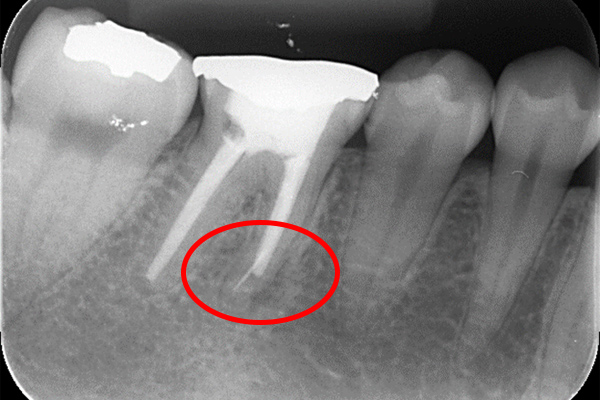

※本来の根管に薬が入ってることがわかります。